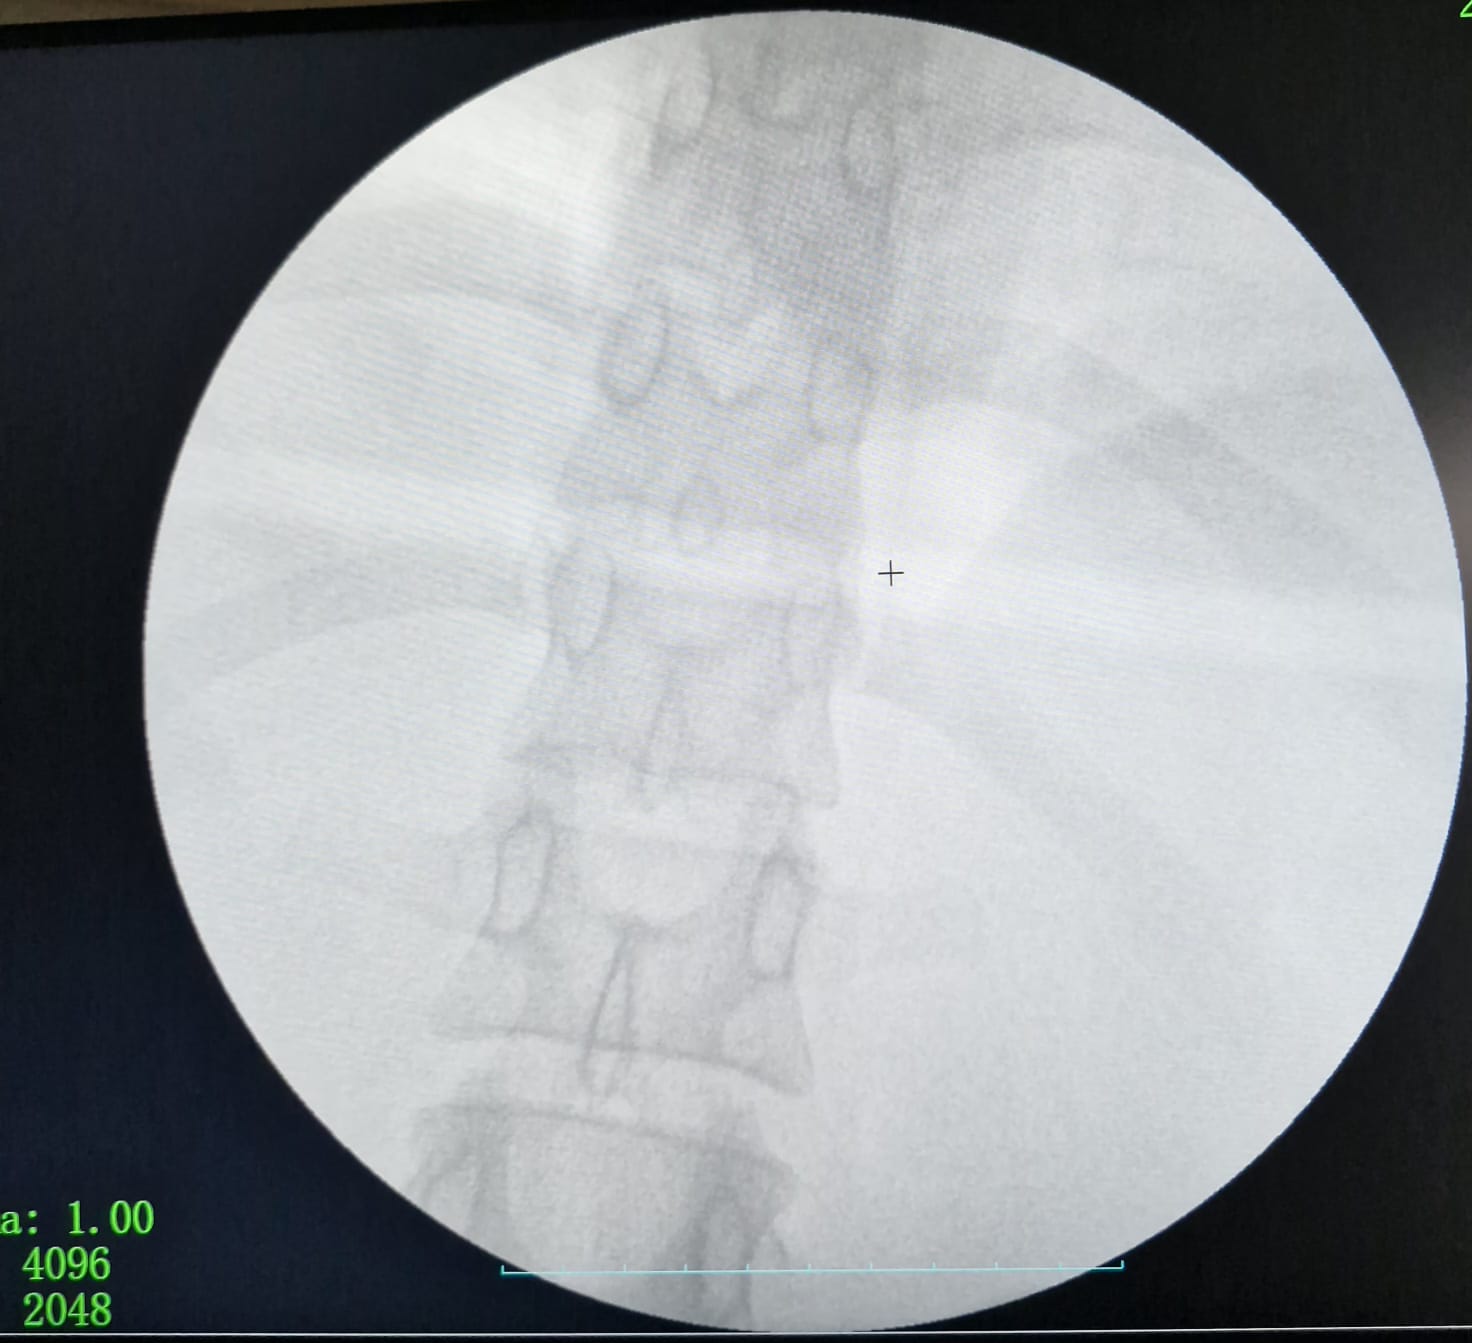

كان المستشفى الرئيسي قد استقبل فتاة تبلغ من العمر ٣٠ عاما، تعاني من آلام حادة ومزمنة بالبطن، ومن خلال تقصي التاريخ المرضي، تبين أنها ابتلعت إبرة خياطة عن طريق الخطأ منذ ما يقرب من ٤٠ يوماً، وعلى الفور، تم إجراء الفحوصات اللازمة والأشعة المقطعية التي أظهرت أن الإبرة لم تكتفِ باختراق جدار المعدة، بل استقرت في موقع تشريحي دقيق جداً بجوار الشريان الكبدي والوريد البابي الكبدي، ليقوم الفريق الطبي الذي ضم كل من، الدكتور محمود حسب النبي، أستاذ مساعد بقسم الجراحة، والطبيب حماده فتحي، والطبيب خالد حسان، والطبيب حسام محمود، مدرسين مساعدين بالقسم، والطبيب ماريو أيوب طبيب مقيم بالقسم، ومن قسم الأشعة التشخيصية والتدخلية، فريق طبي تحت إشراف الأستاذ الدكتور حسن مجلي، رئيس القسم، وضم كل من الدكتور حمدي إبراهيم، أستاذ مساعد بقسم الأشعة التشخيصية، والطبيب ميرنا يوسف، مدرس مساعد بالقسم، يعاونهم فريق طبي من قسم التخدير جاء تحت إشراف الأستاذة الدكتورة هالة سعد، رئيس القسم، وضم كل من الدكتور جورج مجدي، مدرس بالقسم، والطبيب أمونيوس خليل، مدرس مساعد بالقسم، كما عاونهم الأستاذة أماني أحمد، تمريض بقسم الجراحة، والأستاذ حسن علي، فني الأشعة، باستخدام جهاز الأشعة C-Arm، بدلاً من اللجوء إلى الجراحة التقليدية (فتح البطن الاستكشافي)، التي تتطلب وقتاً أطول للتعافي، لرصد مكان الإبرة بدقة متناهية.

ونجح الفريق الطبي في استخراج الإبرة بالكامل باستخدام المنظار الجراحي عبر (٣) فتحات صغيرة فقط في جدار البطن.